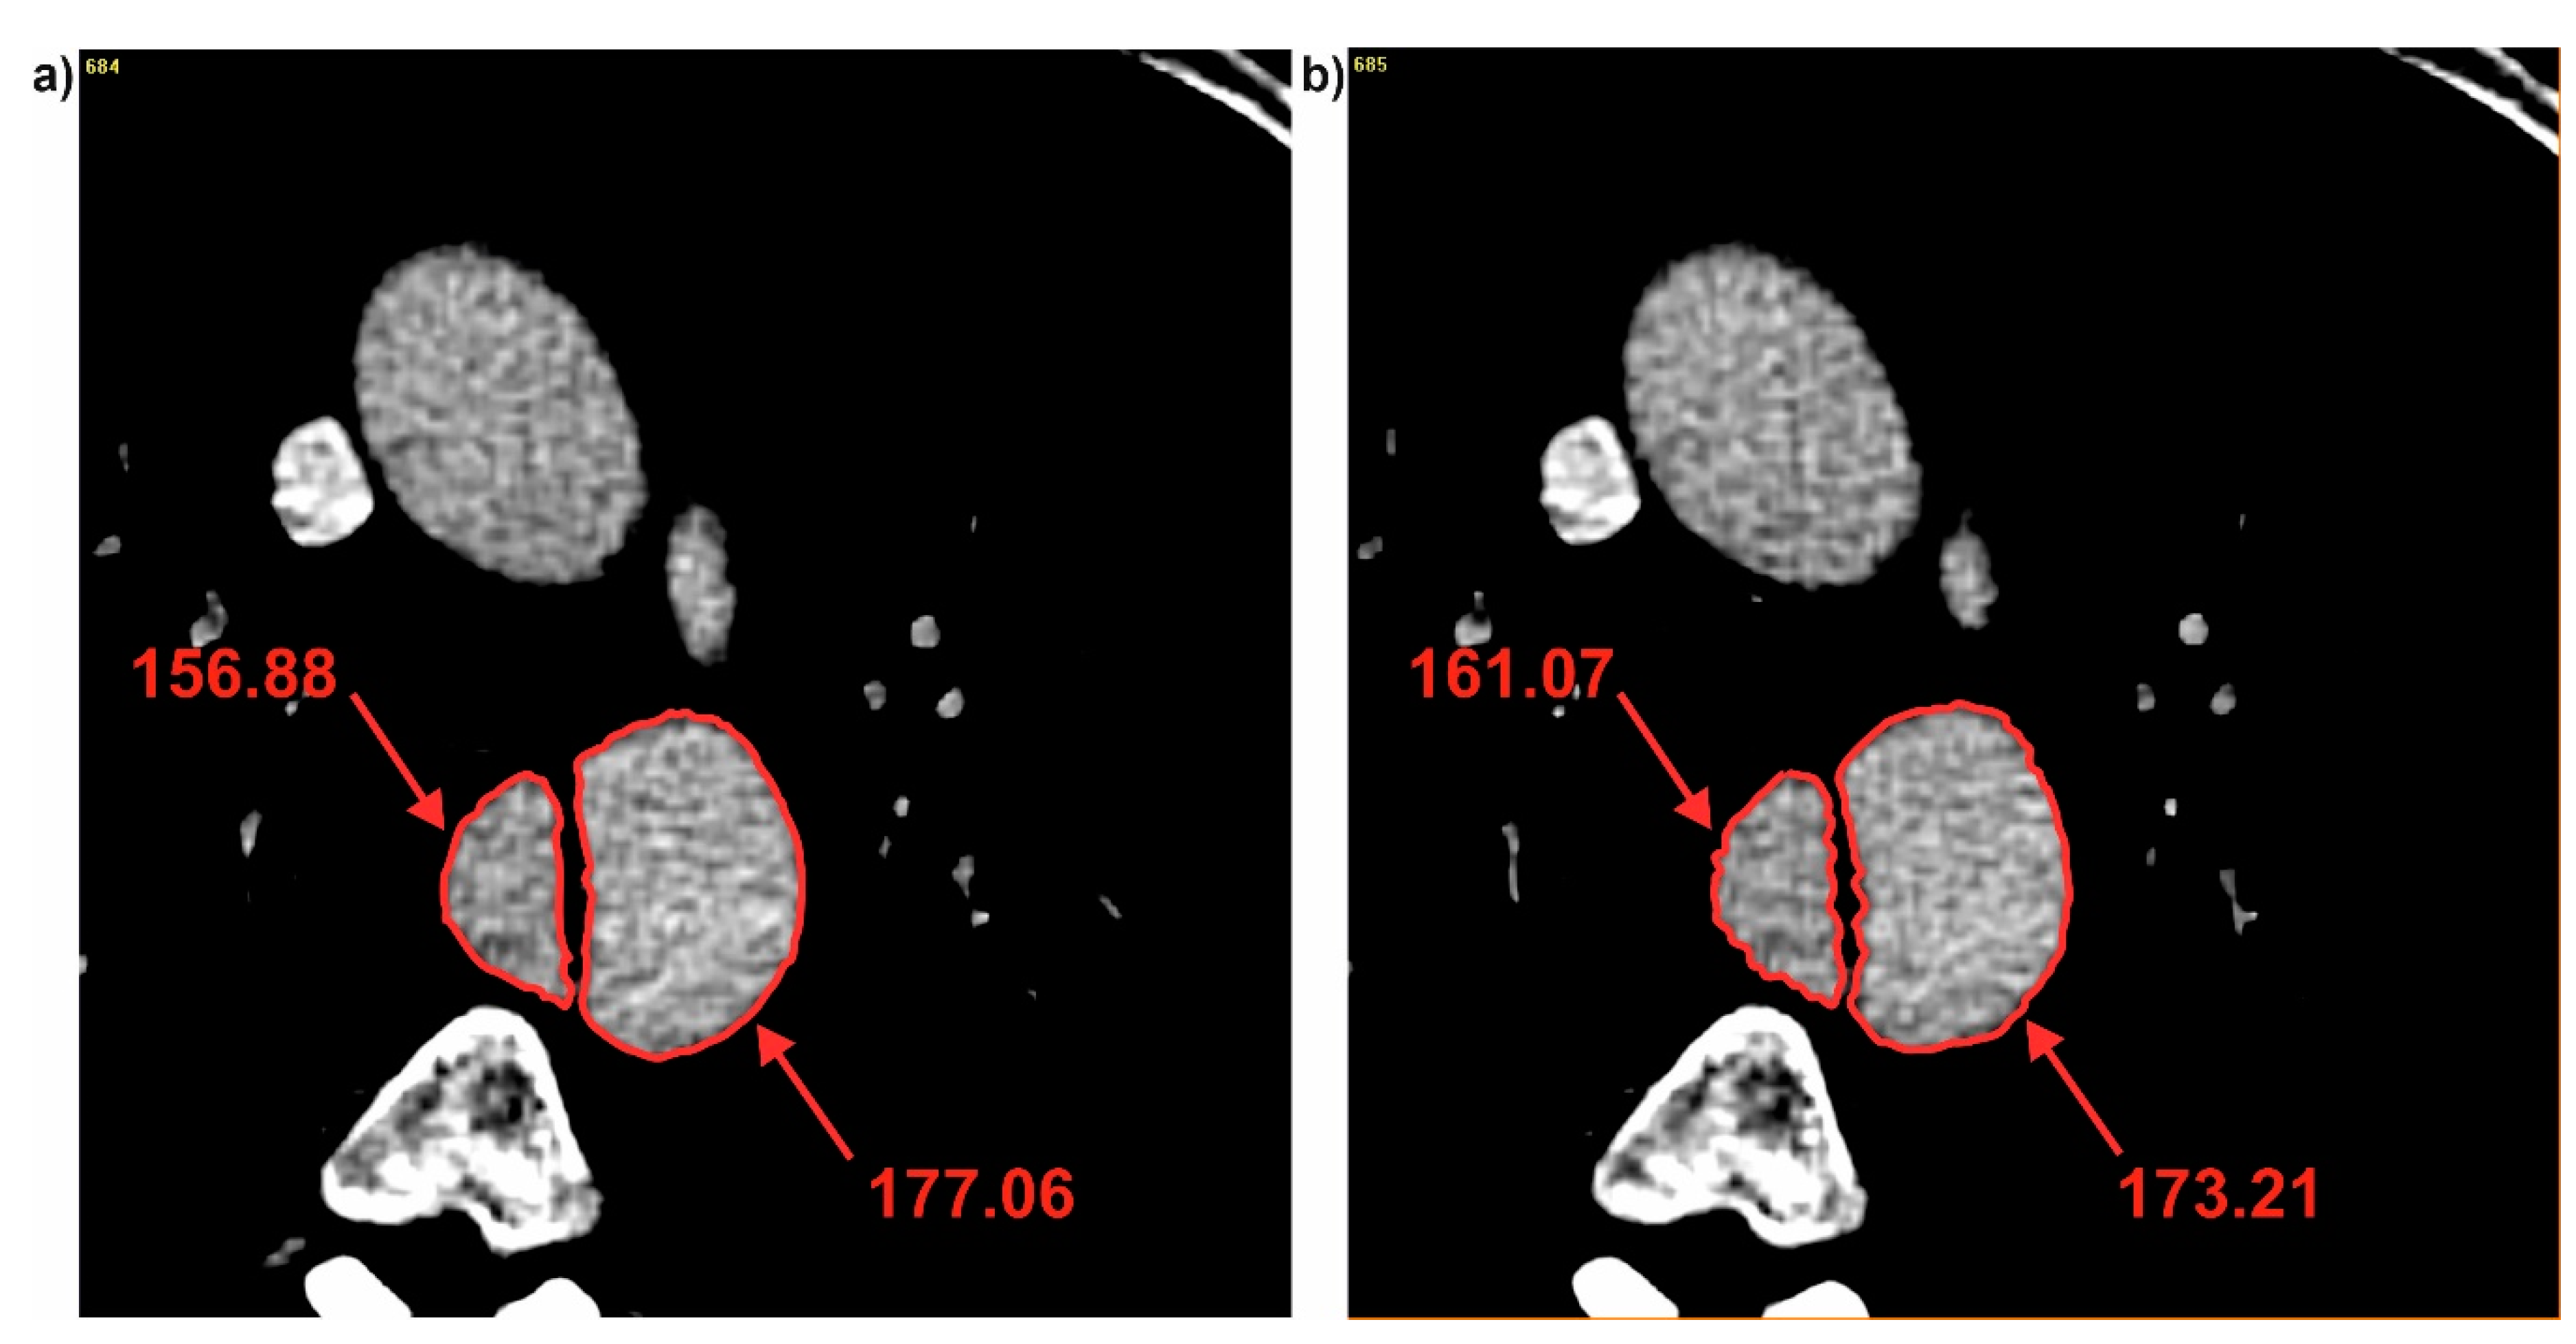

3.2. Brightness Value Analysis

| Patient | Average Brightness | ||

|---|---|---|---|

| Common | True | False | |

| Pat I | 184.73 ± 16.75 | 141.36 ± 20.26 | 178.01 ± 6.04 |

| Pat II | 331.11 ± 18.41 | 364.03 ± 14.10 | 320.10 ± 12.60 |

| Pat III | 291.13 ± 6.60 | 213.52 ± 39.70 | 313.91 ± 8.62 |